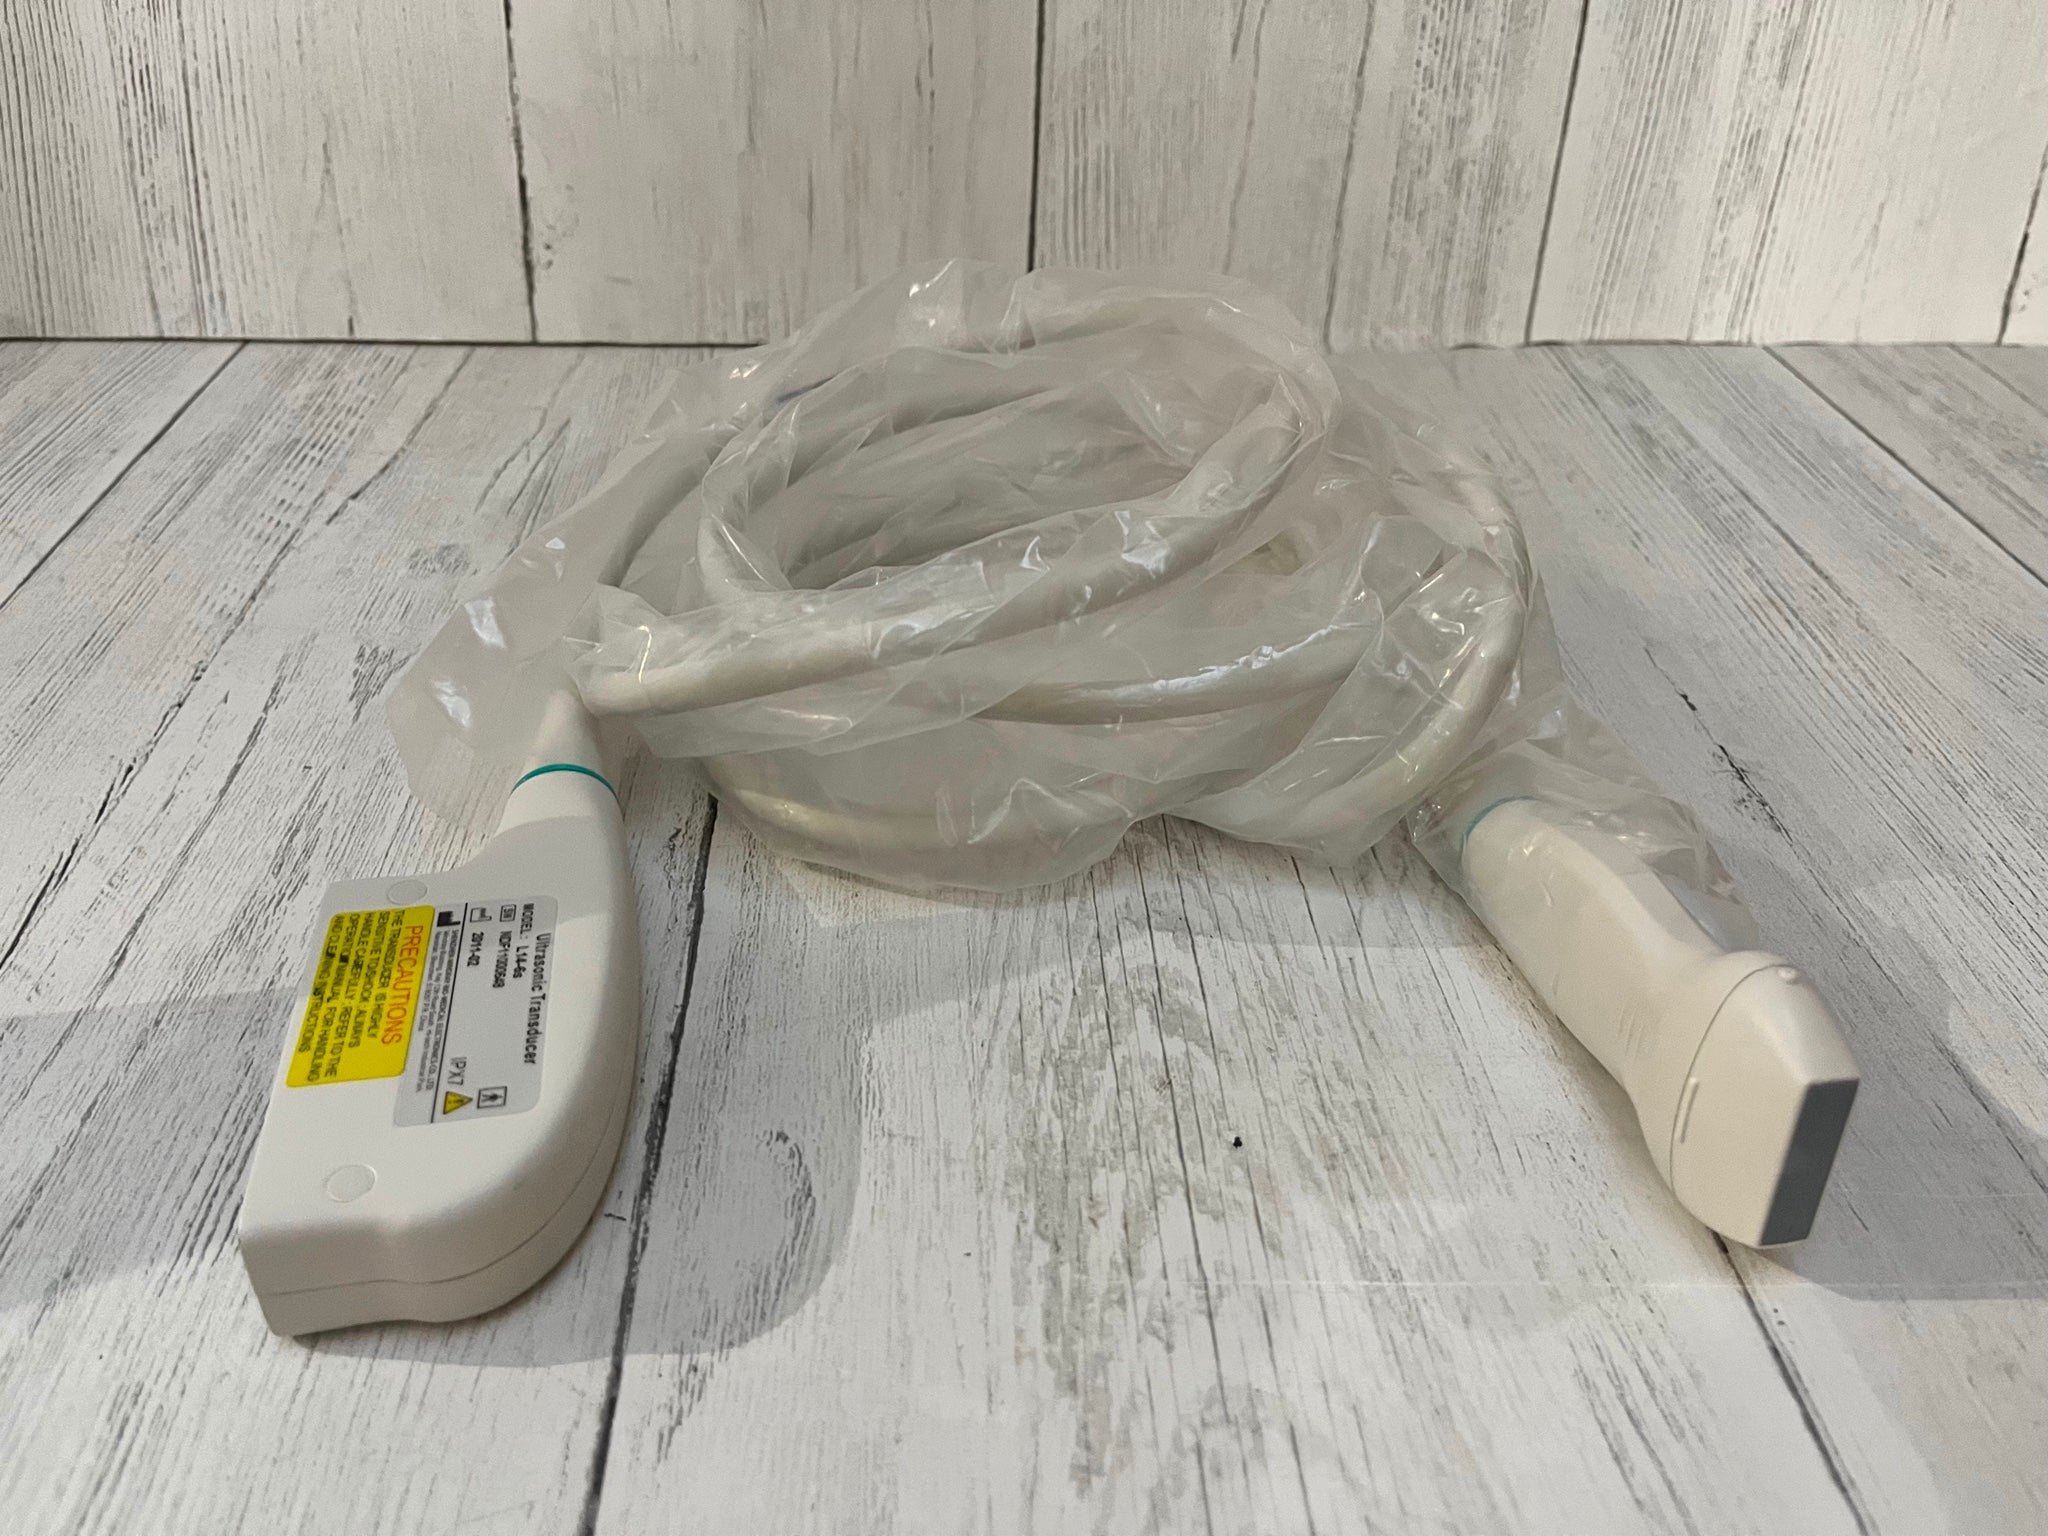

Explore the dependable and sophisticated GE Portable Logiq Book Ultrasound equipped with E8C-RS OB/GYN and 3C-RS Abdominal Transducers. Condition: Gently used with signs of cosmetic wear, yet remains fully operational for accurate diagnostics. Ideal for medical professionals seeking precision with a well-maintained machine. Brand: GE, Model: LOGIQ BOOK. Click to view our detailed listing and invest in advanced medical technology.